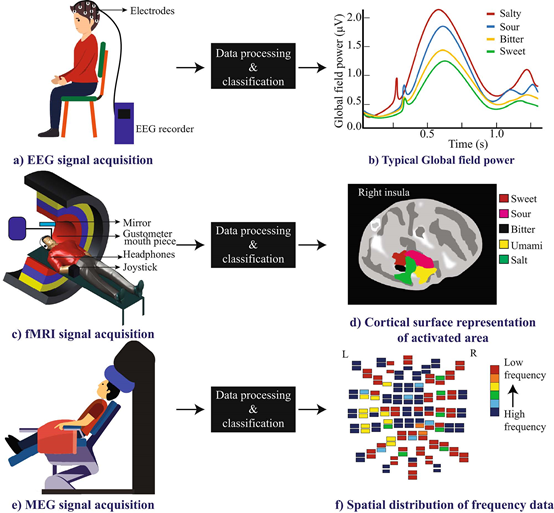

当有一个装置能够利用大脑对各种味觉刺激的反应信号时,BCI系统就可以用于根据我们的味觉反应检索数据。而神经活动信号测量有两种类型;一种基于电生物测量,如脑电图(EEG)、脑磁图(MEG);另一种基于神经活动生理过程的成像技术,如MRI、fMRI、CT扫描、fUS、热成像和PET。对于味觉产生过程,信号的获取往往要求比较高的时空分辨率和较灵活的检测装置,因此用于检测该过程神经活动的技术主要有EEG、fMRI和MEG等。

在采集过程中,被试一般直坐在椅子上,记录味觉任务过程中的EEG信号。电极放置采用国际标准10-20电极系统,由味觉刺激诱发的脑电电位称为事件相关电位(ERP),头皮区域需要用尽可能多的电极进行记录,以获取不同脑区的EEG活动,缩短记录系统的电路,可以有效避免电器噪声。原始EEG包含了兴奋性突触后电流(EPSP)、抑制性突触后电流(IPSP)和伪影噪声(需要去除)。电极通道越多则分析产生的误差越少,一般至少需要16个通道才能获得有分类信息的EEG。目前大多数用64电极系统甚至更多电极通道来提高信号记录效率并降低系统噪声。一般需要足够数量的参与者和重复测试试验次数,以保证结果的可重复性和信噪比(SNR)。EEG中提取味觉信息的提取可以采用时域、频域或时频域的方法。

基于fMRI的BCI技术

fMRI反映神经活动变化是基于神经血管耦合性(BOLD)的原理,即由于特定味觉刺激,局部脑区的活动会引起周围血氧水平上升,这个变化可以通过fMRI图像反映出来。fMRI成像是全脑成像,空间分辨率高,但时间分辨率不如EEG,所以对fMRI的分析一般是以获得不同味觉刺激下分别被激活的脑区以及各脑区之间活动的网络效应为目的。和EEG不同的是,受试者需要以仰卧位躺在扫描床上,头部放置在包含泡沫垫的头部线圈内,由于fMRI成像过程受试无法大幅度咀嚼,所以刺激物一般为液体。fMRI创建了包括时间和三维空间在内的四维数据,数据的初步分析从两个预处理步骤开始,第一个是重新排列过程,通过数据修正来纠正食物品尝过程中口腔器官运动带来的干扰。第二步是归一化,将重组后得到的脑图像装入模板(由蒙特利尔神经学研究所提供),校正个体不同头部大小和形状的影响。在预处理之后,使用参考刺激来识别第一级分析中活跃的大脑区域,将生成β图,在第二级分析中,感觉信息一般使用单变量或多体素模式分析(MVPA)将预处理后的信号数据与beta图进行比较获得。

基于MEG的BCI技术

MEG技术测量神经活动的基础是神经元活动产生电流在内部的交互导致磁感应现象,MEG系统和EEG系统类似,由64通道全头SQUID线圈、脑电图电极、帽线组成,测试环境要避免噪声和磁场干扰。MEG记录过程受试需要保持不懂,所以除了要提前做好沟通之外,还需进行一轮试测,以便受试了解自己的舒适姿势。MEG信号处理主要有以下步骤:预处理将接收到的信号进行分割,去除或减弱其伪影,然后再进一步处理。建模阶段将大脑图像装入一个模板(由蒙特利尔神经学研究所提供)进行形状和大小校正。然后对校正后的图像进行重建,得到所有被试均匀的MEG图像。根据实验范式,将对事件相关响应、学习状态响应和静息状态响应进行数据提取。MEG图像包含空间、时间和频率等多维数据成分。在测量味觉刺激的大脑响应时,一般考虑单个或组合域,并在此基础上提取所需的数据。对味觉刺激MEG信号的分析大多为时频分析,研究发现甜味刺激容易引发低频信号而咸味刺激容易引发高频信号,还有人发现四种味觉刺激对α节律的诱导效应存在性别差异。

三种神经信号监测方法的采集过程和典型的信号输出形式

EEG、fMRI和MEG信号处理步骤